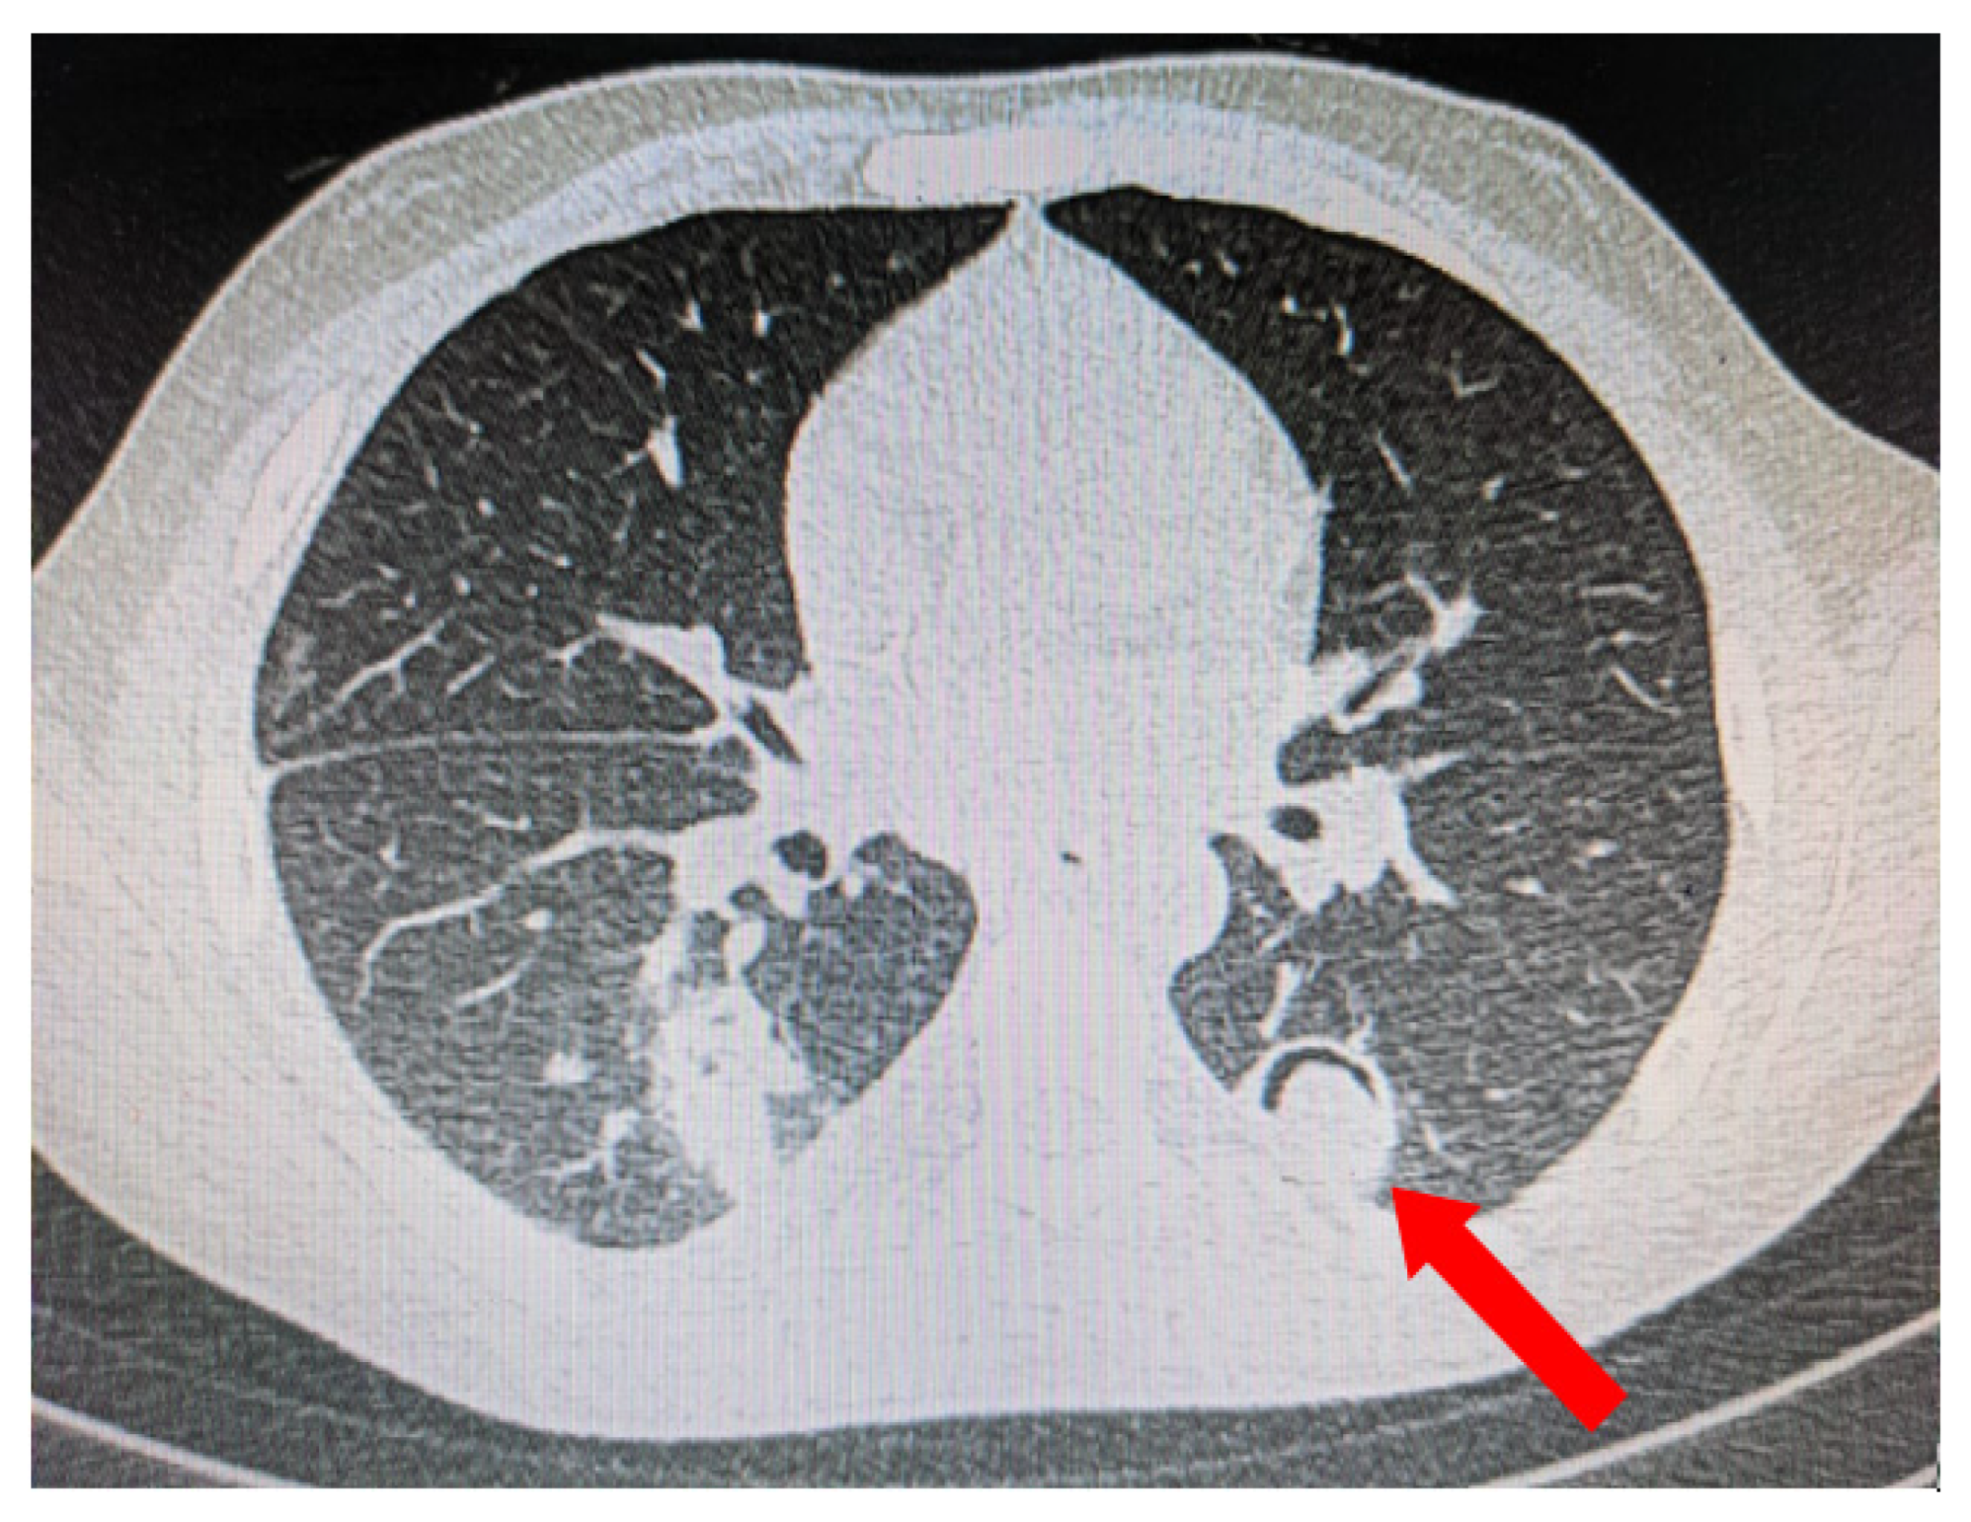

5.1. Role of Diagnostic Imaging

Diagnostic imaging is vital for early detection of invasive mucormycosis in patients with clinical suspicion. Certain distinguishing features of the lung parenchyma on a CT scan of the chest in patients with PM include multiple pulmonary nodules, often pleural-based, presence of lung cavitations and effusions (Figure 1, Figure 2, Figure 3 and Figure 4) [23]. The ‘reverse halo sign’ (central ground glass opacity surrounded by dense consolidation) is highly appreciated, mainly in neutropenic leukemic hosts. In a recent systematic review of CT findings in 16 patients with proven CAPM, consolidation and cavitation were seen in 11 (69%) patients, pleural effusion in 7 (47%), pneumothorax and nodules in 3 (19%) and ‘reverse halo sign’ and pulmonary embolism was seen in 2 (13%) patients [24]. Previously, Nam et al. reported that in hematologic patients, while consolidation and nodules are seen earlier in the disease process, central necrosis, cavitation and the air crescent sign are late findings [25]. This would suggest that CAPM is either under-diagnosed due to lack of differentiation from other fungal, including aspergillosis or bacterial pneumonias, or is diagnosed much later in the illness.

Figure 3. Multiple small nodules (blue arrows). Few show ‘tree in bud pattern’ in left lung parenchyma.

Figure 4. Pleural-based consolidation with cavity and a radio-opaque shadow within the cavity leading to formation of ‘air crescent’ (red arrow).